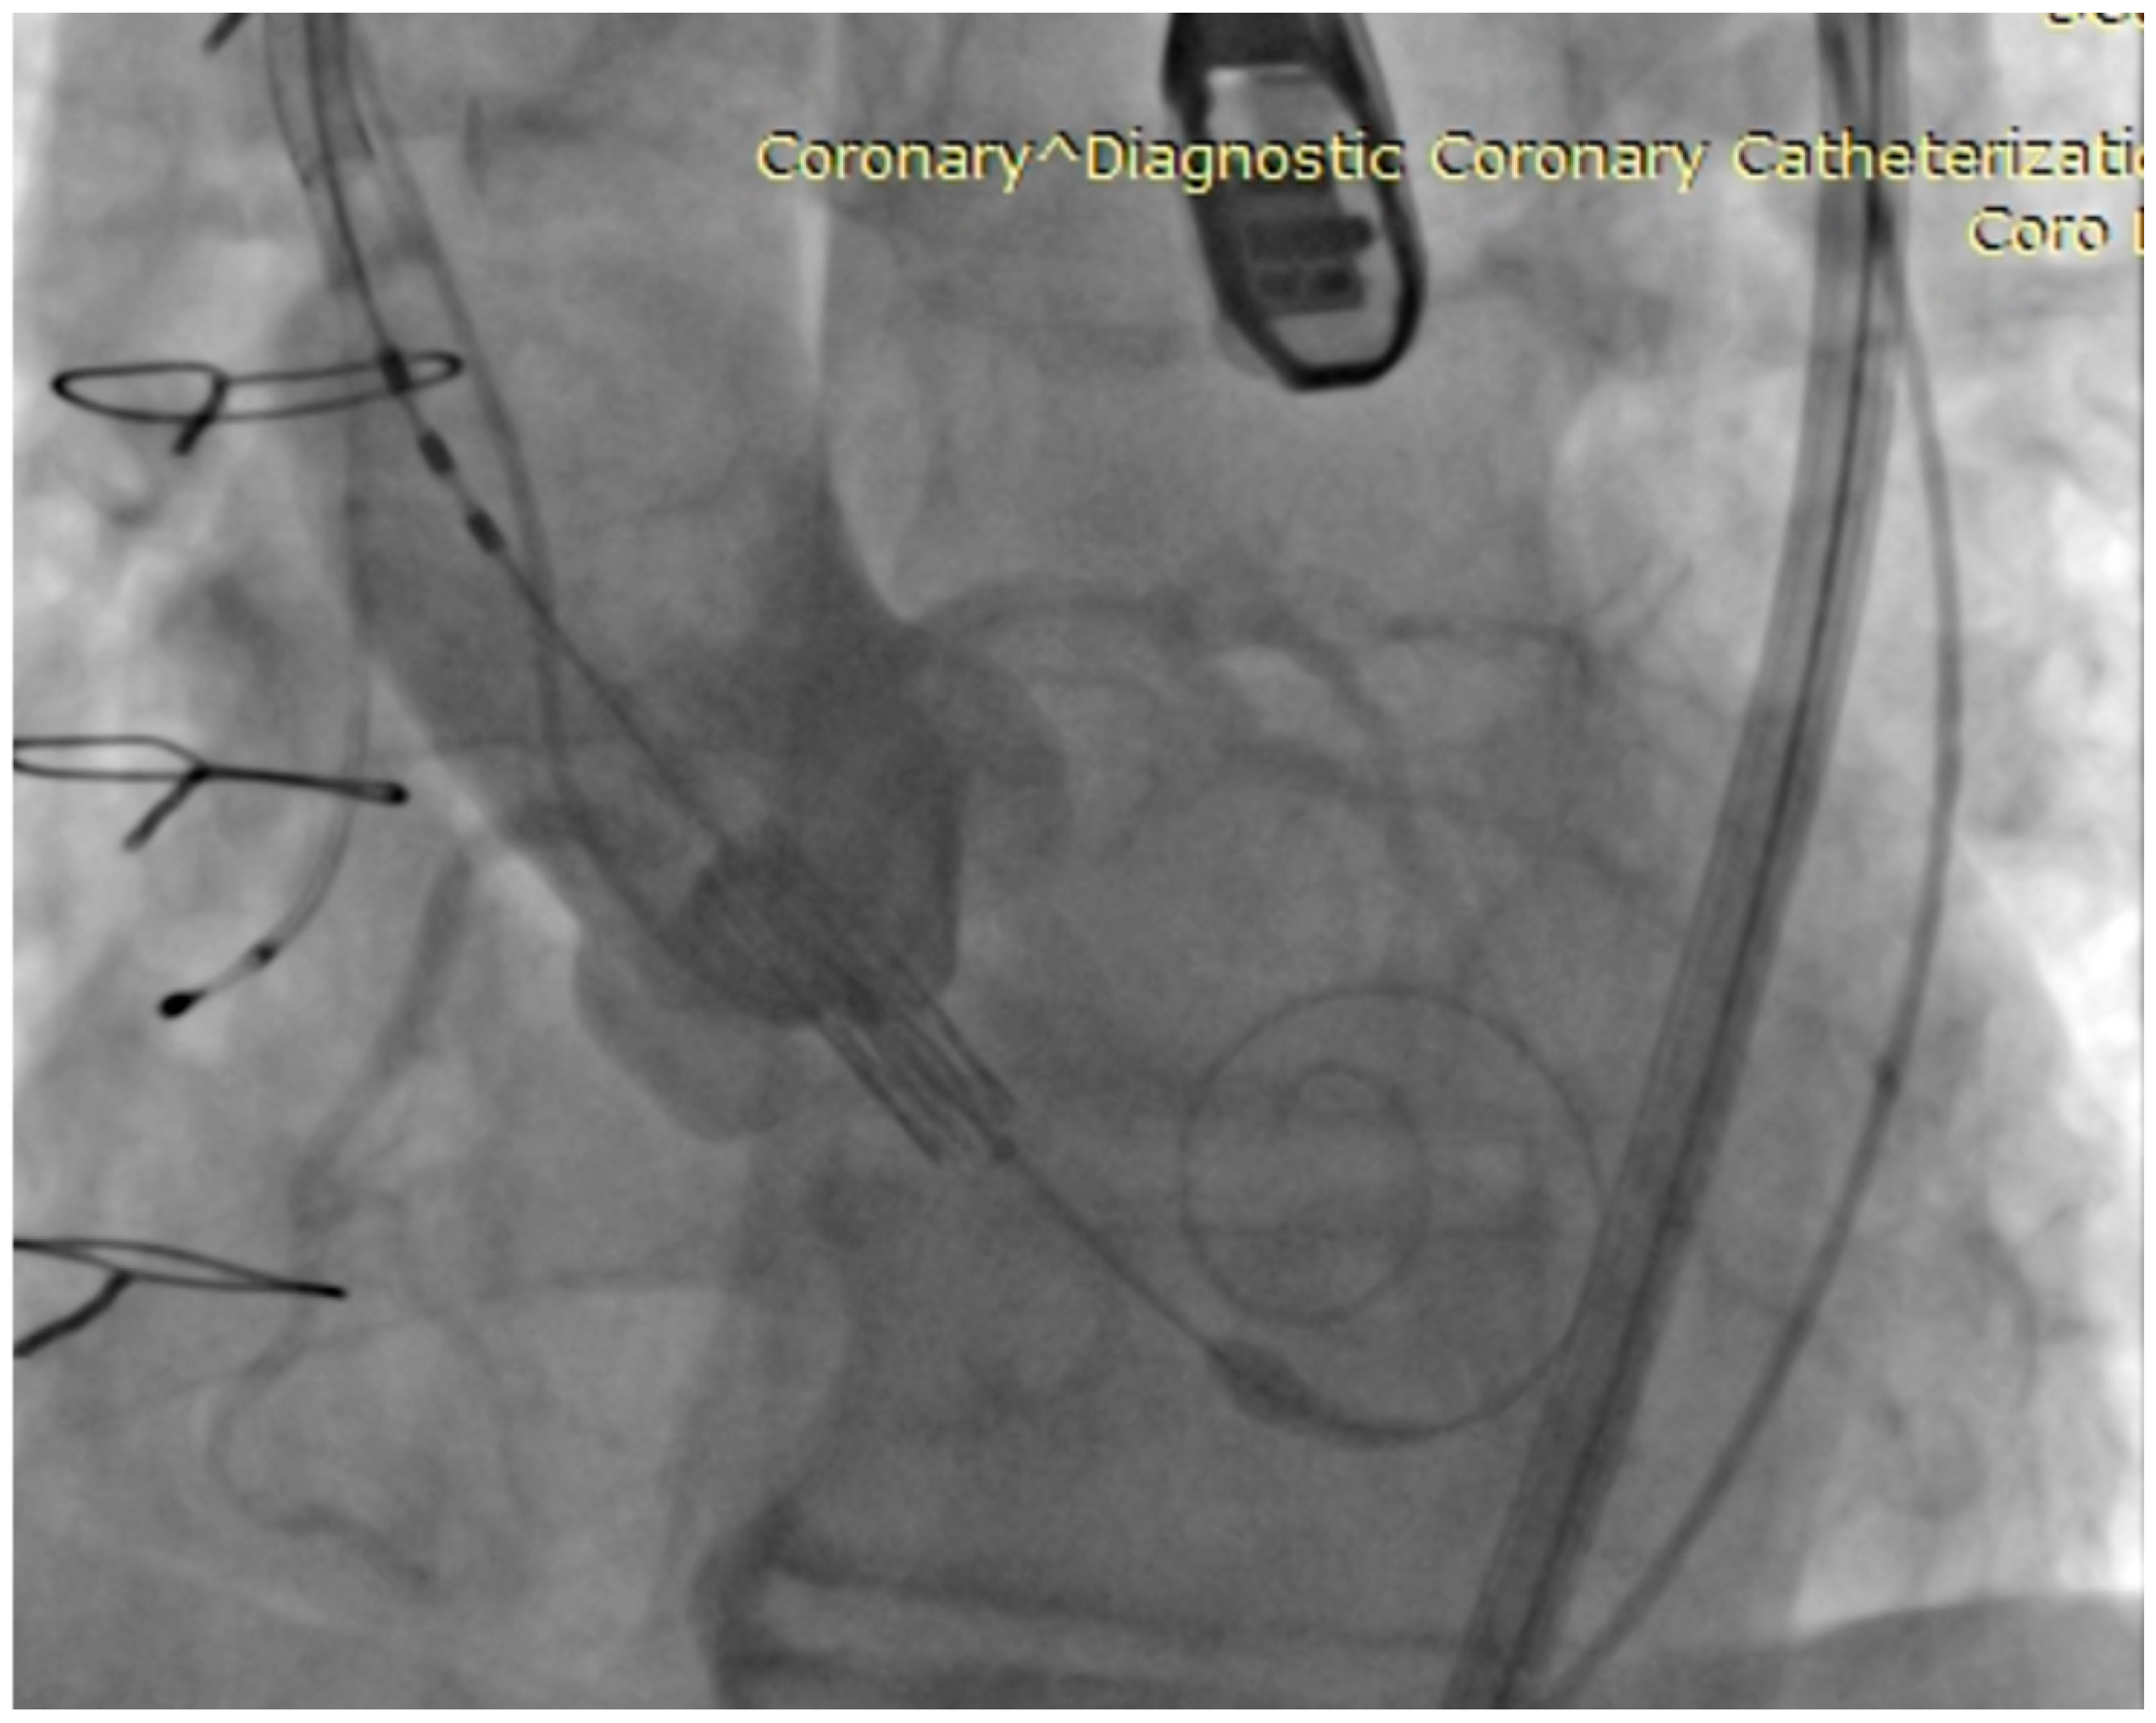

To address the paravalvular leak, a subsequent post-dilation was performed through inflating the valve’s specific balloon with a nominal volume of +2 mL. Fluoroscopy image of aortic root showing baloon inflating in order to expand the aortic prosthesis is observed in Figure 4a, while Figure 4b presents a fluoroscopy image showing inflated baloon in the expanded prosthesis with coronary arteries visible. TEE examination following the post-dilation revealed minimal regurgitation. At the supravalvular aortic injection, only mild regurgitation was observed. Figure 5 presents a fluoroscopy image where checking the valve position and regurgitation can be observed. The guidewires were then carefully withdrawn, and another TEE confirmed minimal residual regurgitation. Hemostasis was achieved through the use of Proglide and Angioseal devices following the removal of guidewires and sheaths.

Figure 4. Fluoroscopy images of aortic root—baloon inflating in order to expand the aortic prosthesis (a) and inflated baloon in the expanded prosthesis with coronary arteries visible (b).

Figure 5. Fluoroscopy image—Checking the valve position and regurgitation.